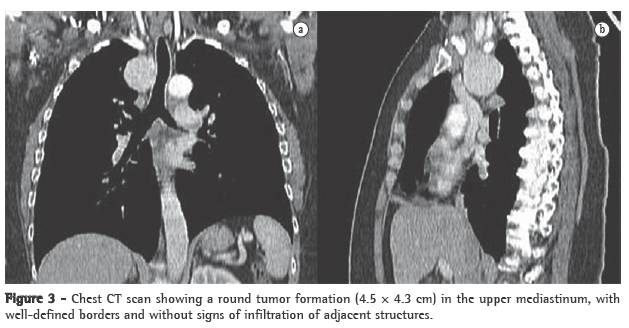

A CT scan of the chest revealed, in the upper mediastinum, a round, extensive formation (4.5 × 4.3 cm), without signs of infiltration and with well-defined borders, located laterally between the superior vena cava and the right contour of the trachea (Figure 3).